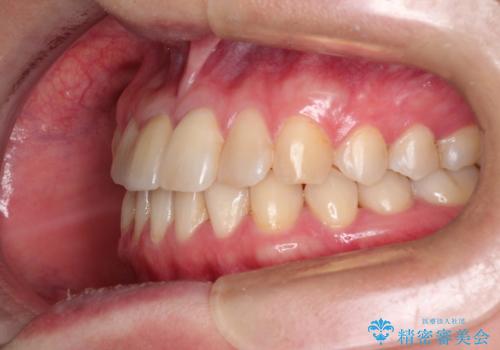

- 前歯の歯並びが気になるとのことで来院されました。

右上の1番目の歯が内側に入り込んでしまっており、その歯がの先端がすり減ってしまっていました。

インビザラインによる矯正治療で前歯の歯並びを改善し、セラミッククラウン装着により歯の形態の回復をする計画としました。

矯正とセラミックを併用することで、より完成度の高い状態に仕上げることができました。